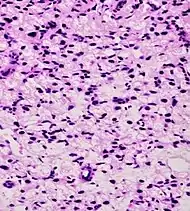

Small-cell carcinoma 0.3–2%[14][15][notes 1]

• Small blue cells with scant cytoplasm[1]

• High nucleus/cytoplasm ratio[1]

• "salt and pepper" chromatin[1]

• Nuclear molding[1]

• Necrosis of single cells, or geographic[1]

• Smearing artifacts[1]

Half of cases have usual acinar components[1]